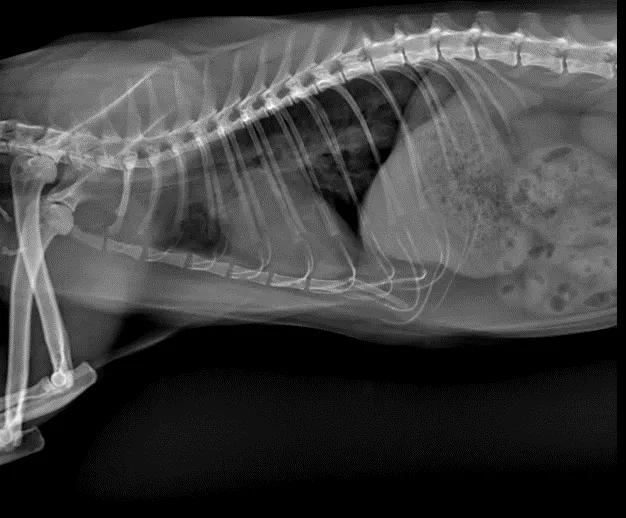

X光检查:右侧位与腹背位显示,肺门处影像学密度上升,心影整体偏大。